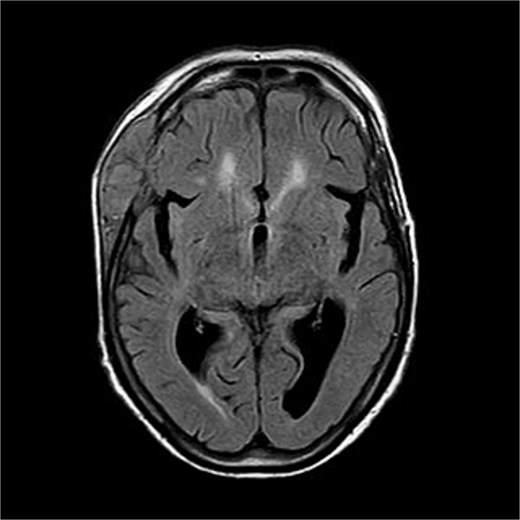

A 70-years old female came to the tertiary hospital, with a gradually enlarging right frontal-temporal scalp swelling associated with headache. She presented to the ER with abnormal movement, described by the son was gazing upward toward specific point with right upper limb jerky movement lasting for 15 s and frothy secretions, not responding during the event. Whole event lasted for 40–45 s. No reported pre-event symptoms and for post event patient was back to baseline after one-to-one hour and half. The son noticed this event repetitively happens on exertion, positioning the patient from lying to siting position, and before the dialysis sessions. Regarding her surgical and medical history, she is a known case of type 2 diabetes mellitus, hypertension, end-stage renal disease on dialysis, and cardiac disease with low ejection fraction. In addition, the patient had undergone a total abdominal hysterectomy with bilateral salpingo-oophorectomy under spinal anaesthesia in for endometria carcinoma, stage IB, grade 2 and subsequently received vaginal vault brachytherapy. Upon physical examination, the patient was noted to have a large, non-tender, soft to firm swelling in the right frontal-temporal region, with no other remarkable findings. CT with contrast (Figs 1 and 2) of the brain revealed metastasis to the right frontal bone and the greater wing of the sphenoid, with large extra-cranial and small intracranial soft tissue components with no parenchymal brain lesions were observed. A brain biopsy confirmed that there was fibromuscular and adipose tissue with focal necrosis and atypical cells, with crushed and scarse atypical cells likely neoplastic or reactive. Also, PET CT scan (Figs 3 and 4) confirms that there was brain metastasis sparing lymph nodes. Given her poor status and significant comorbidities, she was deemed unfit for systemic chemotherapy. The patient received palliative radiotherapy to the scalp lesion 20 Gy in 5 fractions.

There is a bone lesion involving the right frontal bone and, to a lesser extent, the right greater wing of the sphenoid, with a sizable extracranial soft tissue component in the temporal fossa measuring 5 × 1.8 × 5.4 cm in CC, TV, and AP dimensions respectively. There is also a small related intracranial extra-axial soft tissue component with associated pachymeningeal mild thickening and enhancement over the frontotemporal cerebral convexity. No obvious brain parenchymal invasion is noted, No midline shift or brain herniation. There is generalized brain tissue volume loss in the form of prominence of sulci, gyri, and ventricular system. A tiny focus of blooming effect is noted at the right cerebellar hemisphere.